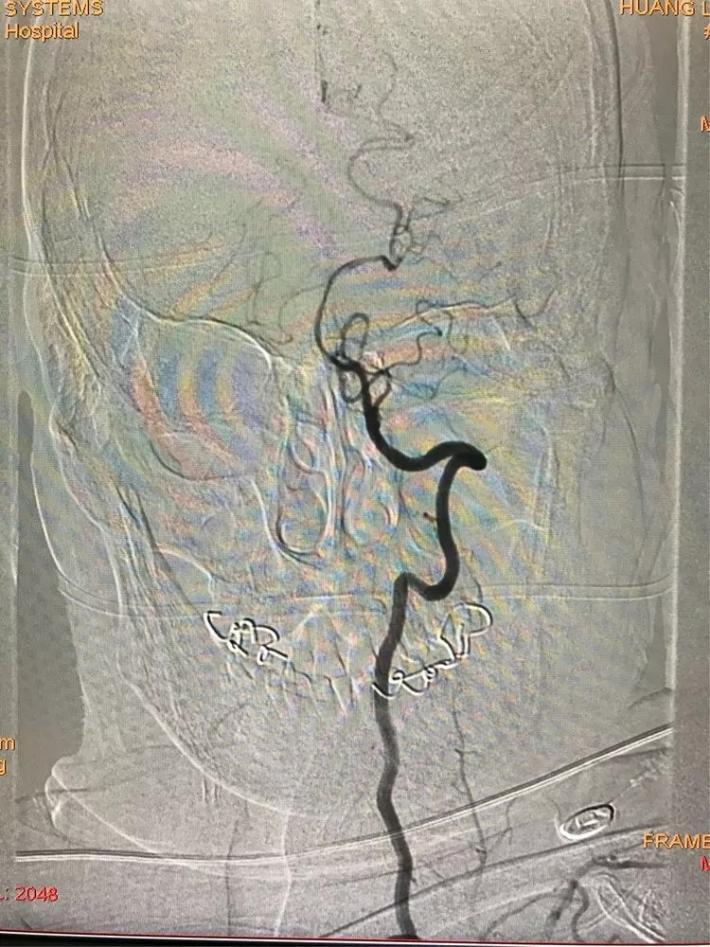

脑血管造影显示:右侧大脑中动脉闭塞。

手术步骤

微导管进入大脑中动脉远端真腔。

置入支架,见大脑中动脉有血流。

取出支架,血管未开通。

再次上微导管。

微导管进入大脑中动脉远端真腔。

第二次置入支架取栓。

血管仍未开通。

第三次上微导管。

再次置入支架取栓。

见血管再通。

支架和取出来的血栓。